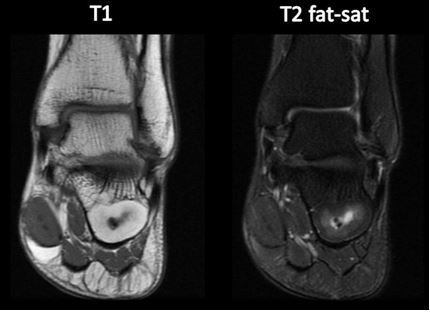

RESSONÂNCIA MAGNÉTICA

Vantagem da RM?

CORTES ALÉM DO AXIAL (CORONAL, SARGITAL, OBLIQUO)

PODE FAZER SUPRESSÃO DE GORDURA NAS SEQUÊNCIAS